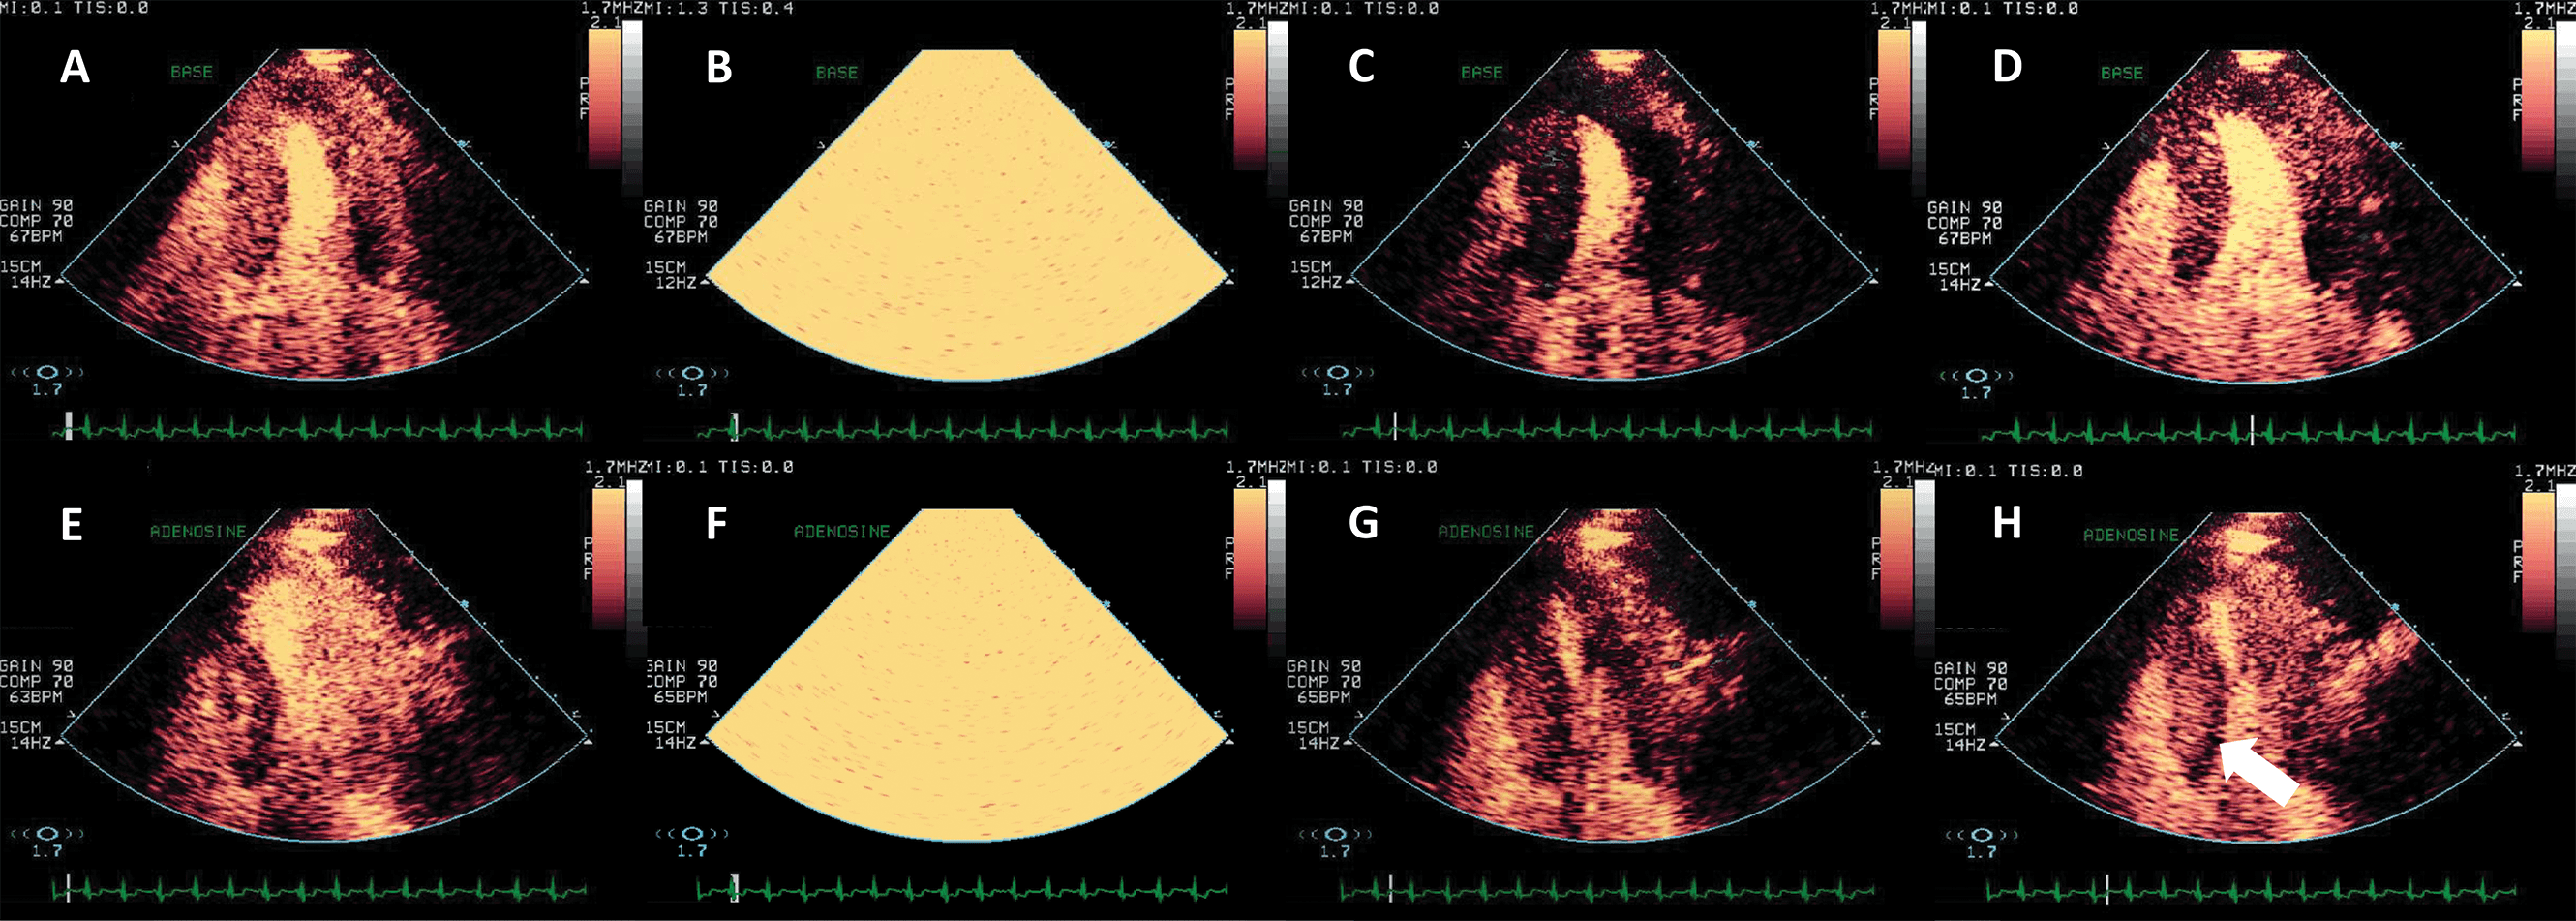

Assessing myocardial perfusion has incremental benefit over wall motion analysis in detecting coronary artery disease (CAD) [55]. The myocardial contrast signal obtained in a steady state (continuous infusion) can be normalized to the LV cavity signal and this represents the myocardial capillary volume [54]. By delivering a series of high-power (high mechanical index) ultrasound frames to the region of interest, cavitation and destruction of the UEA bubbles is initiated; the analysis of the progressive recovery of the contrast signal in the myocardium provides information on the myocardial capillary flow [54, 55, 56] (Fig. 9, Video 8).

Fig. 9.Vasodilator stress echocardiography with Adenosine, using a low-MI setting and flash-replenishment technique. (A–D) Baseline end-systolic frames before flash (A), flash (B), immediately post flash (C, myocardium is dark because of the destruction of contrast), and post-replenishment frame (D) when perfusion is again homogeneous. (E–H) After adenosine infusion, the same order of frames. (H) Post replenishment end-systolic frame demonstrating a subendocardial perfusion defect in the inferosetptal segements (arrow). Of note, during stress myocardial replenishment occurs faster than at rest because of the pharmacological vasodilation. The patient underwent coronary angiography and stent placing in the right coronary artery. Source: personal collection.

The sensitivity and specificity of myocardial contrast stress echocardiography in detecting CAD are 83% and 79% respectively for a vasodilator stress (dipyridamole or adenosine) and 88% and 77% respectively for dobutamine or exercise stress studies [7, 57]. Two large multicenter studies demonstrated superior sensitivity of myocardial perfusion stress echocardiography as compared to SPECT, but lower specificity [58, 59]. The higher sensitivity may be due to the fact that SPECT only detects the myocardial blood volume, and not the kinetics of myocardial blood flow, as opposed to contrast-enhanced stress echocardiography, which can assess both [54]. The lower specificity may be related to artefacts during stress echocardiography, mainly in the apex (near-field destruction) and basal segments (far field attenuation in apical view).